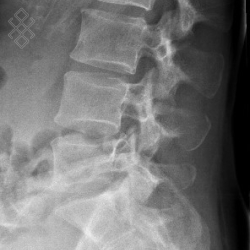

Radiographie du Rachis lombaire

La durée de l'examen est d'environ 5 minutes. Un ou plusieurs clichés radiographiques seront effectués. Le manipulateur vous positionnera en fonction de l'incidence radiologique à réaliser. Sauf indication contraire, il sera important de ne pas bouger durant la prise de clichés.